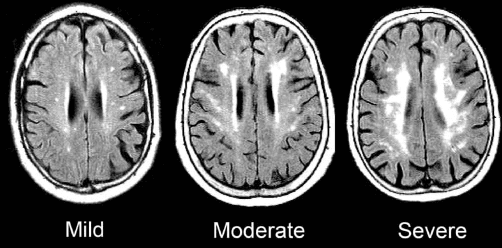

What Are They? White Matter Hyperintensities are areas in the brain that show up as bright spots on certain brain scans. They indicate areas where the white matter (the brain’s “wiring”) is not as healthy as it should be.

Key imaging biomarkers:

| White Matter Hyperintensities | Bright spots indicating damaged areas | More WMH often means more cognitive problems |